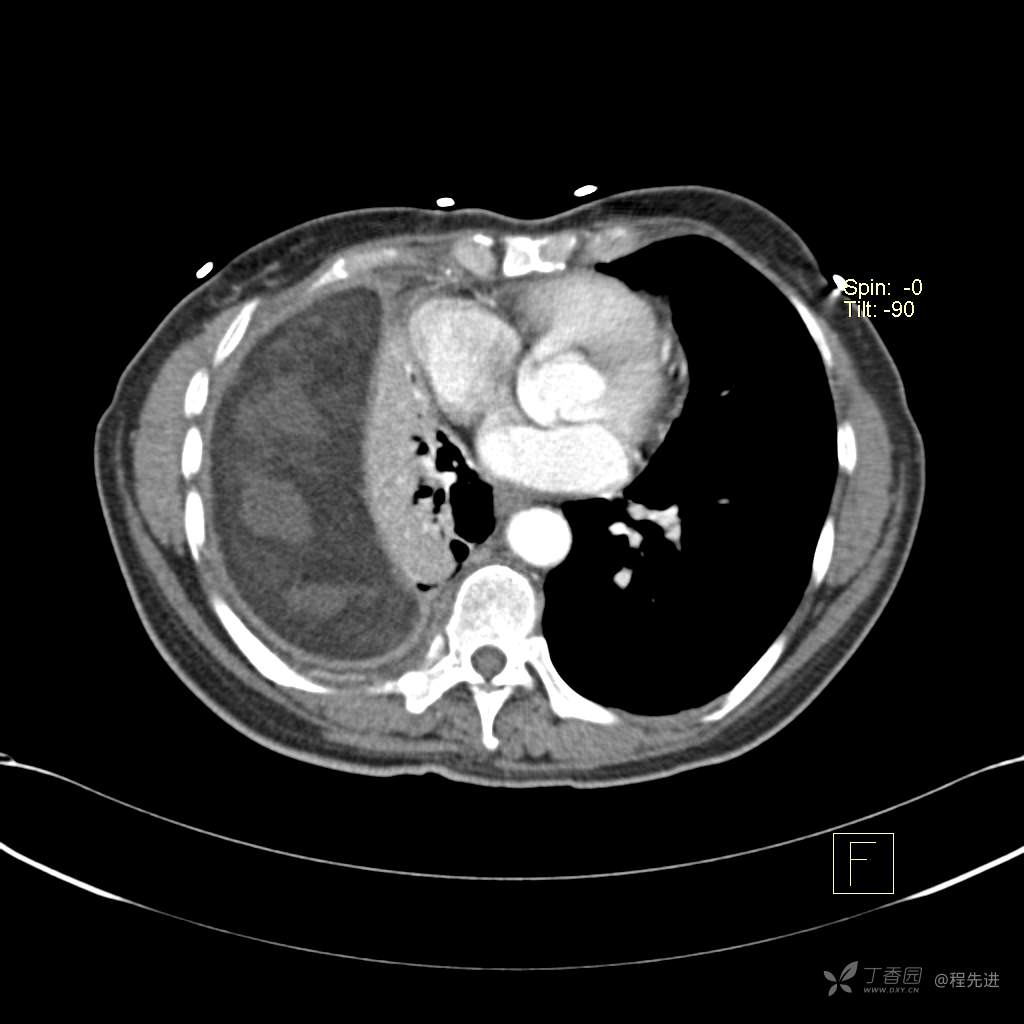

患者性别:女

患者年龄:51岁

简要病史:胸闷半年